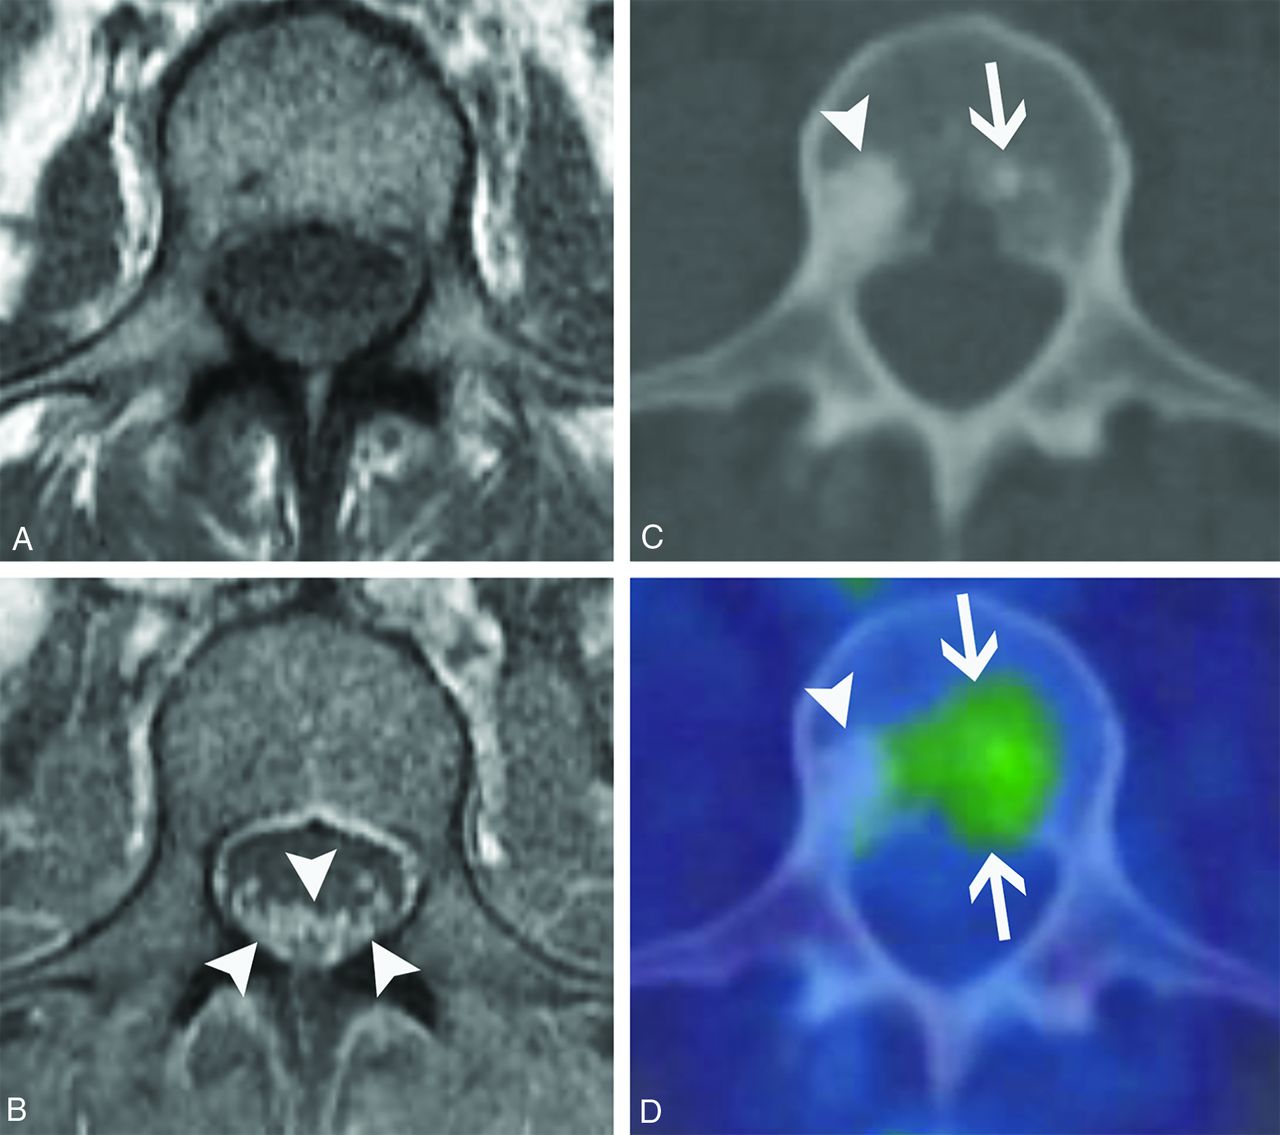

Reports of imaging findings of paraneoplastic polyneuropathy involvement are scarce. To our knowledge, there are only 5 published cases of paraneoplastic polyneuropathy showing cauda equina abnormalities. These have demonstrated variable patterns of enhancement, with 2 patients having ANNA-1 positivity.27,29-32 We have found that enhancement can predominantly involve the dorsal (Fig 8) or ventral nerve roots (Fig 9), and the pattern of enhancement does not always correlate with symptoms. The clinical presentation can frequently mimic Guillain-Barré syndrome with a similar rapidly ascending weakness (Fig 8). Additionally, polyneuropathy may be seen with osteosclerotic multiple myeloma in the setting of POEMS syndrome (polyneuropathy, organomegaly, endocrinopathy, monoclonal plasma proliferative disorder, skin changes).33 Although POEMS syndrome is not always described among the classic forms of PNS, many authors consider its peripheral nerve involvement to be paraneoplastic. The presence of sclerotic bone lesions and peripheral nerve root enhancement are the most important imaging features to suggest POEMS syndrome (Fig 10).

Paraneoplastic polyneuropathy mimicking Guillain-Barré syndrome. A 69-year-old woman presented with rapidly progressive ascending weakness and paresthesias. CSF analysis was remarkable for albuminocytologic dissociation, and the patient was initially diagnosed with Guillain-Barré syndrome. Sagittal T1-weighted pre- (A) and postcontrast (B) and axial T1-weighted pre- (C) and postcontrast (D) images from the patient’s lumbar spine MR imaging show enhancement of the predominantly dorsal cauda equina nerve roots (B–D, arrowheads). There is relative sparing of the ventral nerve roots (D, arrows), somewhat atypical for Guillain-Barré syndrome. The patient’s CSF was later found to be ANNA-1/anti-Hu antibody positive, and she was ultimately found to have small cell lung cancer.

Ventral predominant paraneoplastic polyneuropathy. A 29-year-old man with a history of mediastinal seminoma presented with progressive lower extremity weakness and frequent falls over months. Lumbar puncture showed elevated CSF IgG. Serum and CSF were positive for Kelchlike protein 11 autoantibodies. Sagittal T1-weighted pre- (A) and postcontrast (B) images, as well as corresponding axial T1-weighted pre- (C) and postcontrast (D) images from his lumbar spine MR imaging demonstrate smooth enhancement of the cauda equina nerve roots with a predilection for the ventral roots (B and D, arrows). There is clear sparing of the dorsal roots (B and D, arrowheads). He was diagnosed with paraneoplastic polyneuropathy and had mild symptomatic improvement with numerous immunosuppressive agents.